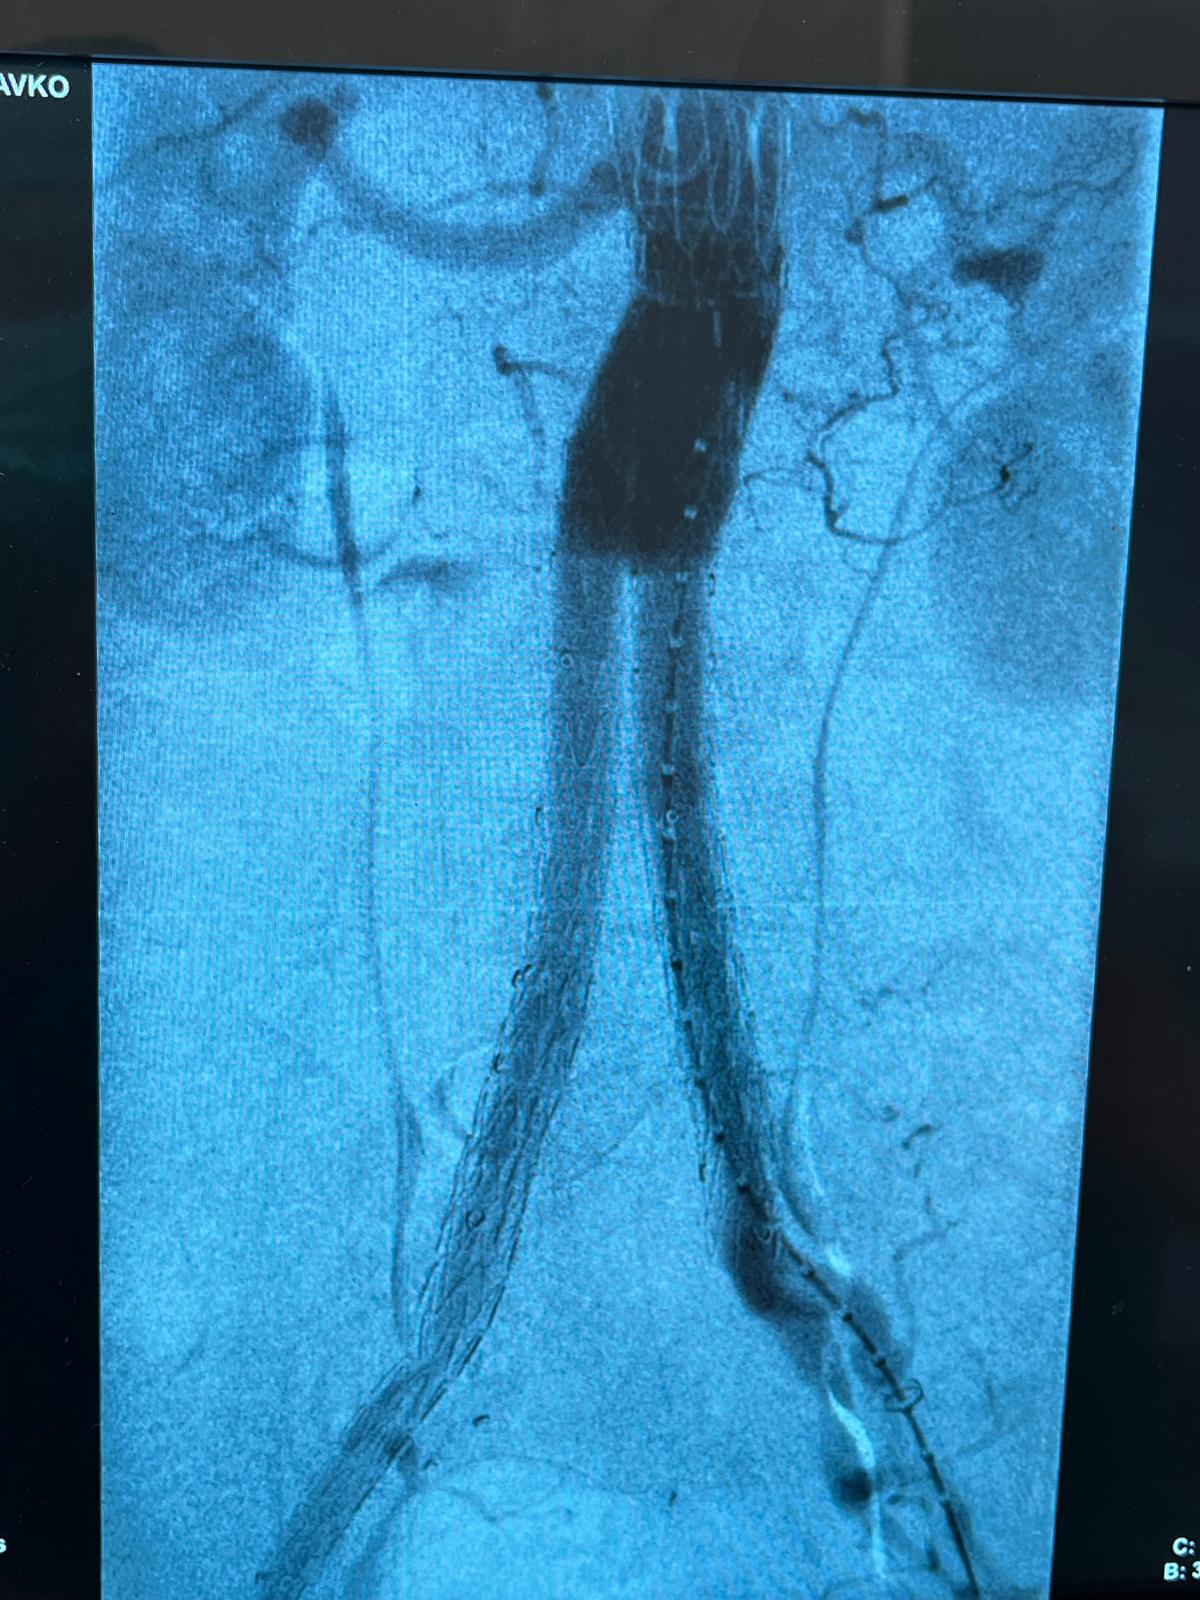

Pod budnim okom iskusnih kolega iz KBC Osijek docenta Tomislava Ištvanića i doktora Vedrana Farkaša, bjelovarski vaskularni kirurzi Damir Kopek i Marko Mladić napravili su veliki iskorak u liječenju najtežih krvožilnih bolesti. U Općoj bolnici Dr. Anđelko Višić Bjelovar uspješno je izvedena prva operacija aneurizme abdominalne aorte EVAR metodom. Riječ je o minimalno invazivnom zahvatu koji pacijentima donosi brži oporavak.

Time je bjelovarska bolnica postala prva opća bolnica u Hrvatskoj u kojoj je takva operacija izvedena. Posebnu težinu ovom uspjehu daje činjenica da je riječ o tek drugom timu u zemlji, nakon Osijeka, koji ovakav zahvate izvode vaskularni kirurzi bez interventnih radiologa i kardiologa.

Pacijent, 70-godišnjak s bjelovarskog područja čija je aneurizma imala promjer 6 centimetara, zahvat je podnio bez komplikacija, a operacija je prošla u najboljem redu.